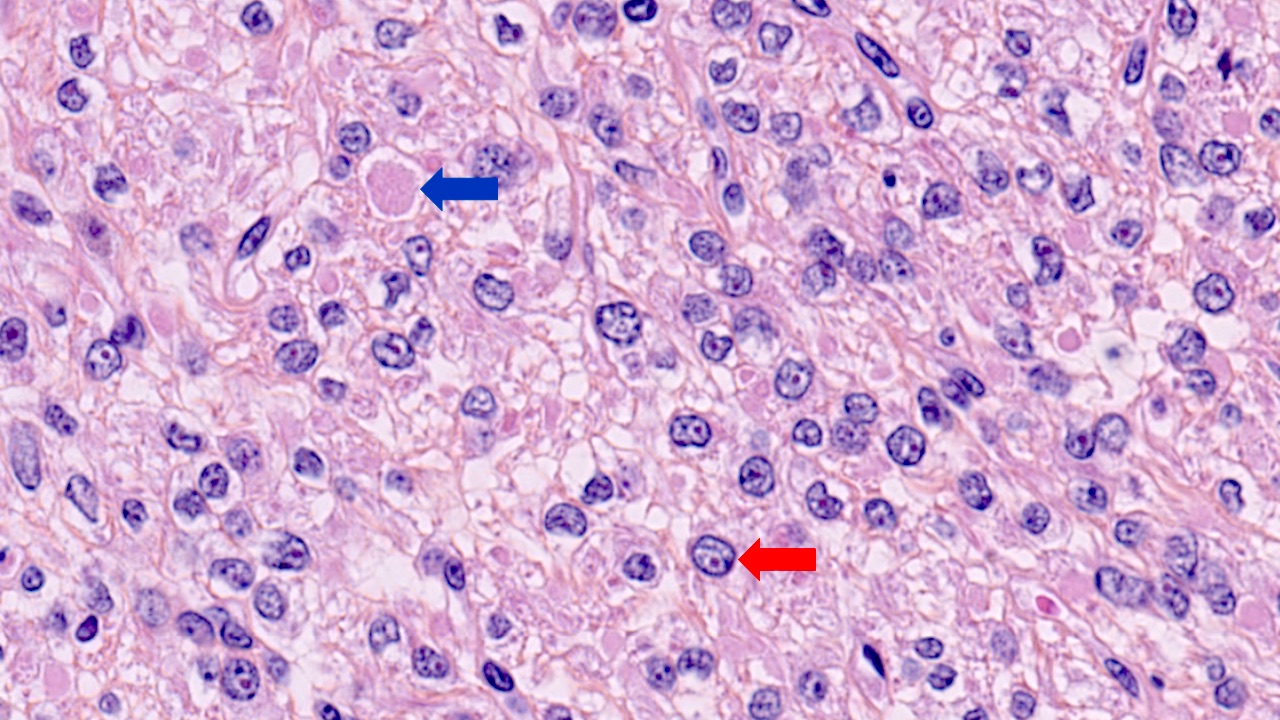

Microscopic (histologic) images

Contributed by Sabrina Croce, M.D., Ph.D., Kristina Doytcheva, M.D., Jennifer A. Bennett, M.D. (Case #508) and @Andrew_Fltv on Twitter

- Leiomyoma with bizarre nuclei:

- Bizarrely shaped, hyperchromatic, multilobulated nuclei with nuclear pseudoinclusions

- Arranged in a multifocal to diffuse distribution in a background of a typical leiomyoma (Am J Surg Pathol 2014;38:1330, Mod Pathol 2017;30:1476, Am J Surg Pathol 2016;40:923, Cancer 2014;120:3165, Am J Surg Pathol 1997;21:1261)

- Alveolar edema, staghorn vessels

- Low mitotic activity (< 5 mitoses/10 high power fields)

- Absence of tumor cell necrosis

- Vasculature variable (staghorn vessels, thick walled vessels, fibrinoid necrosis of vessel walls, luminal vascular obliteration)

- Diagnostic key: intermixed normal spindled smooth muscle cells